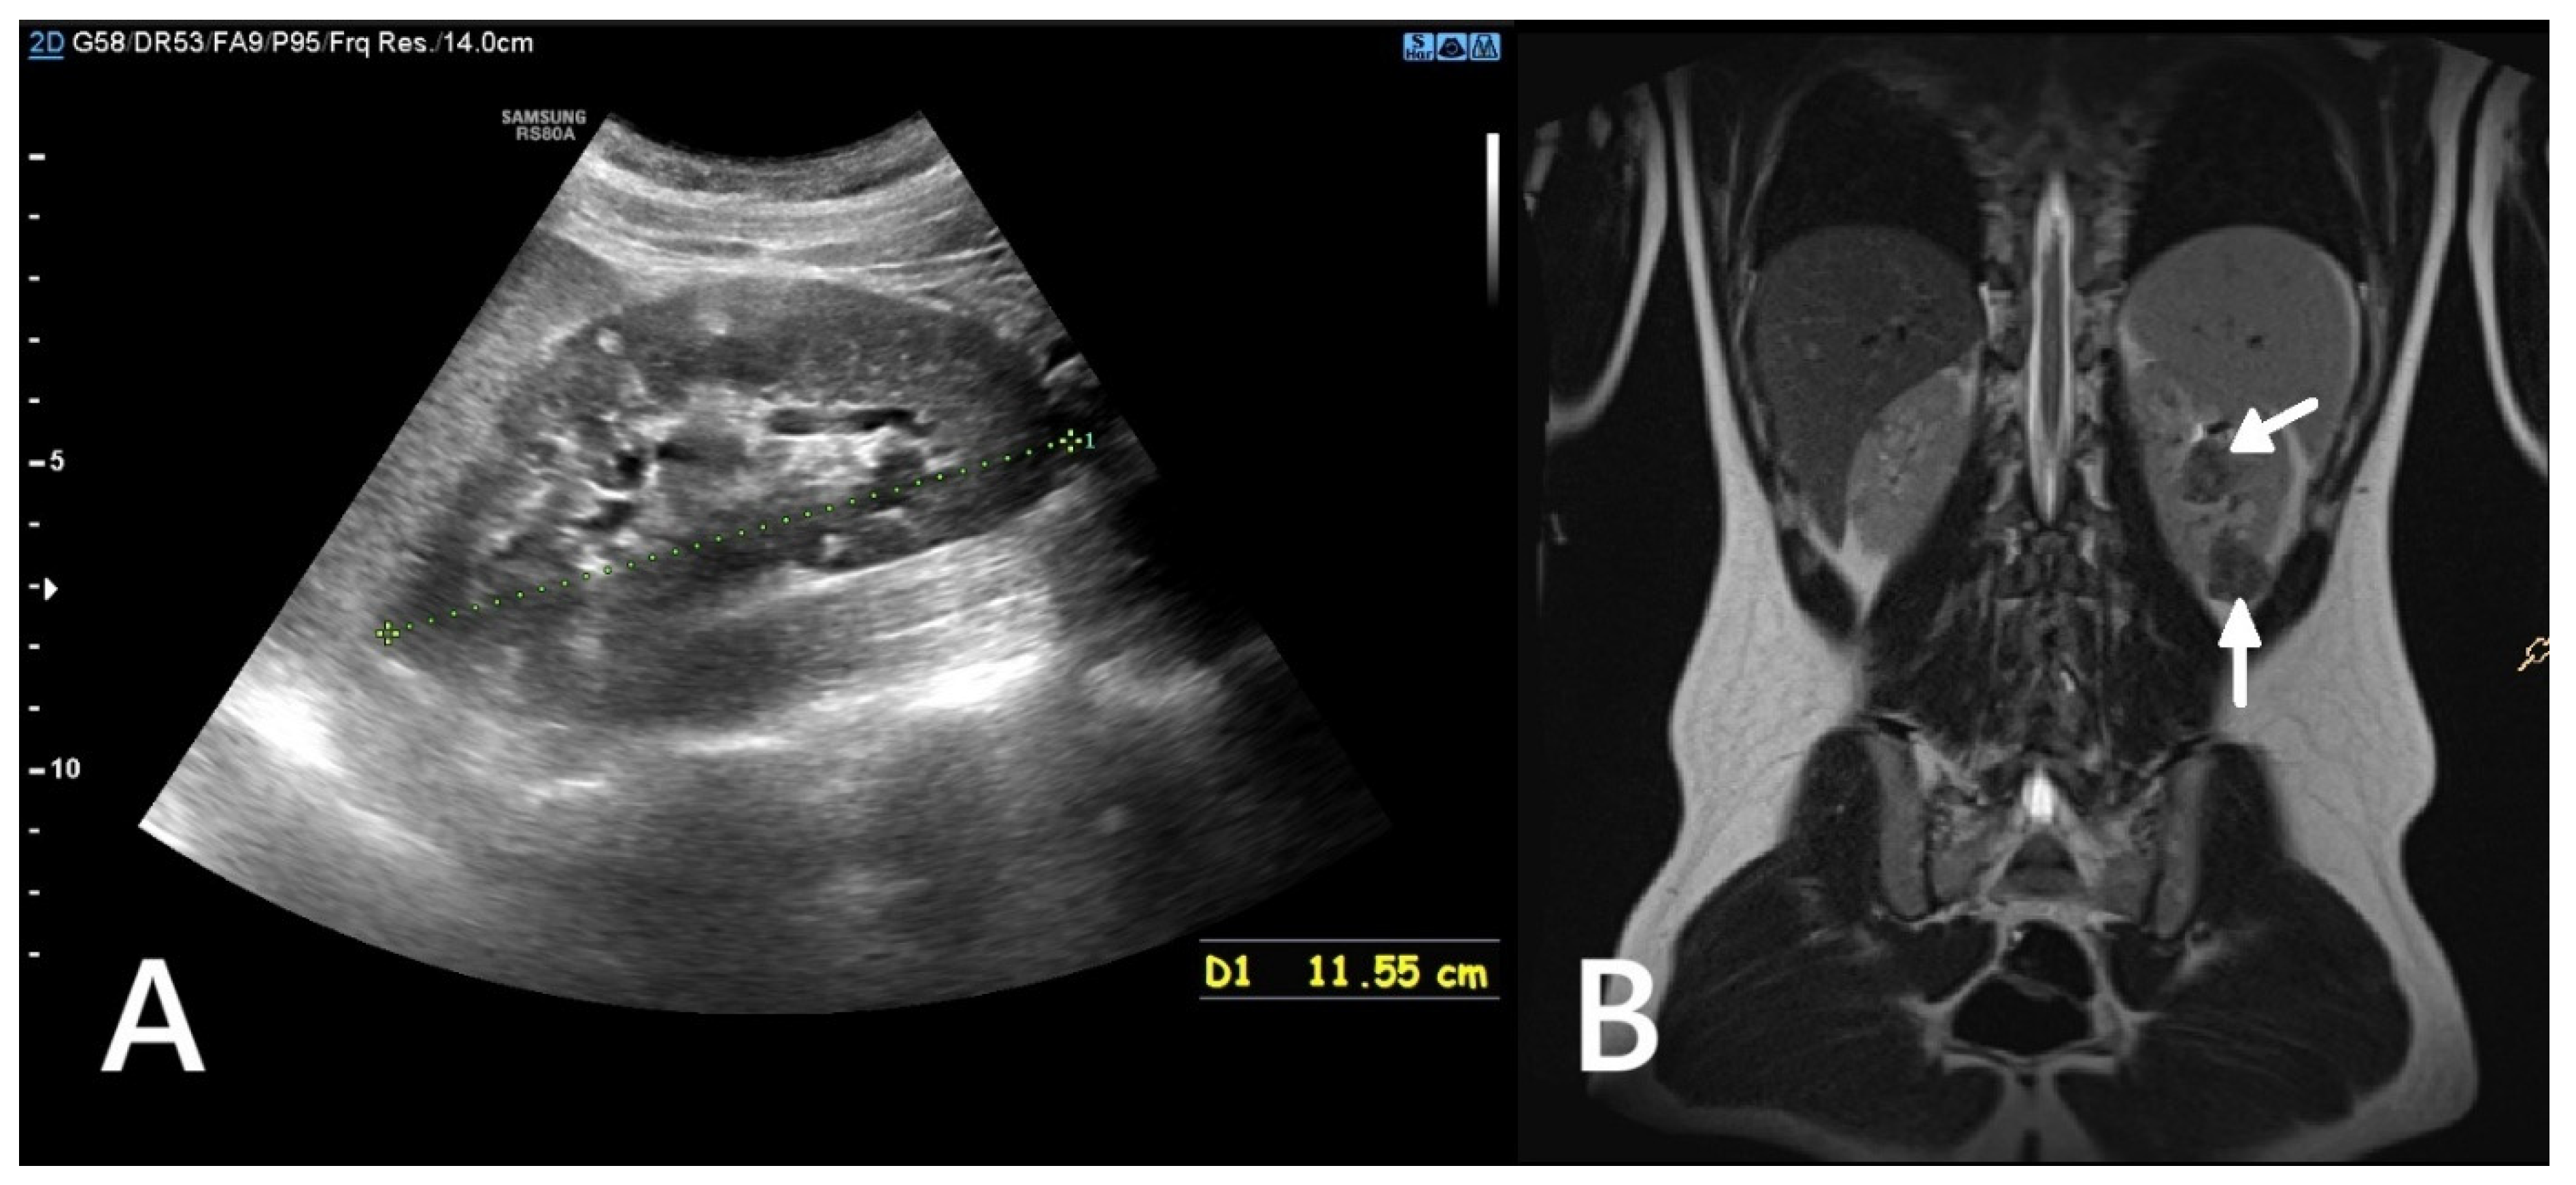

3.3. Polycystic Kidney Disease in Children with Tuberous Sclerosis Complex

In 2–3% of patients with TSC, TSC2/PKD1 contiguous gene syndrome (CGS) is found as a distinct disease entity with clinical features typical of TSC combined with severe and early polycystic kidney disease, almost always associated with early progression to end-stage renal disease (Figure 3). The TSC2 and PKD1 genes lie in a slightly overlapping tail-tail position on the short arm of chromosome 16 (16p13.3), and the cause of the disease is a large deletion involving the 3′ end of TSC2 and extending to the neighbouring PKD1, encoding polycystin-1. There appears to be a spectrum of variability in disease severity and prognosis for CGS, reflecting allelic variation and tissue mosaicism.

Figure 3. An MRI without (A) and with a contrasting agent (B) of a 3-year-old boy with a contiguous gene deletion syndrome involving TSC2/PKD1. Both kidneys are markedly enlarged, containing numerous thin-walled cysts of varying shapes. The remaining renal parenchyma is severely deformed.

As with ADPKD, subtle cortical hyperechogenicity and renal enlargement may be evident on prenatal ultrasound in patients with CGS. Similarly, an infant or young child with TSC who presents with hypertension associated with enlarged, cystic kidneys may also have CGS. In milder cases, only genetic testing can distinguish the polycystic TSC phenotype from the CGS phenotype [23]. In addition to the potentially severe cystic phenotype, patients with CGS are also predisposed to developing renal masses due to TSC2 mutations. These masses present the same challenges as in TSC patients without PKD1 mutations. Consequently, renal imaging in CGS should follow the stricter TSC guidelines, recommending annual MRI or CT, rather than the protocols used for ADPKD [24].